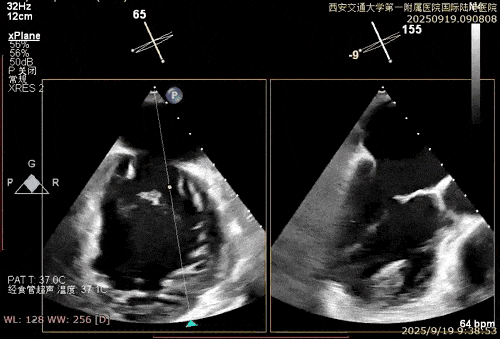

术中在超声引导下完成房间隔穿刺,将第一枚XTR在左房内完成终定位,2偏3区完成植入,夹合效果良好,即刻超声显示轻微反流,完成夹子释放,手术效果良好,手术圆满结束,患者术后6小时即实现床旁活动。